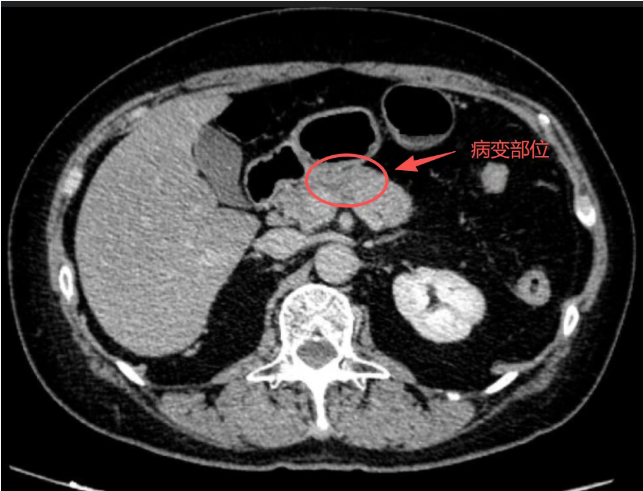

华声在线1月12日讯(通讯员 万燕 李健)近期,长沙市民吴女士(化名)在体检中,意外发现胰尾部存在低回声结节。经多方咨询后,她选择在长沙市第一医院(中南大学湘雅医学院附属长沙医院)普外一病区(肝胆外科)接受进一步诊疗。入院完善检查后,CT及磁共振结果显示胰腺尾部存在肿瘤可能。在科室主任、主任医师熊立新的带领下,医疗团队组织了多学科会诊(MDT)。经MDT讨论,该患者被诊断为胰腺尾部恶性肿瘤,肿瘤未见明确血管侵犯、远处转移及典型淋巴结转移,当前最优治疗方案为根治性手术。